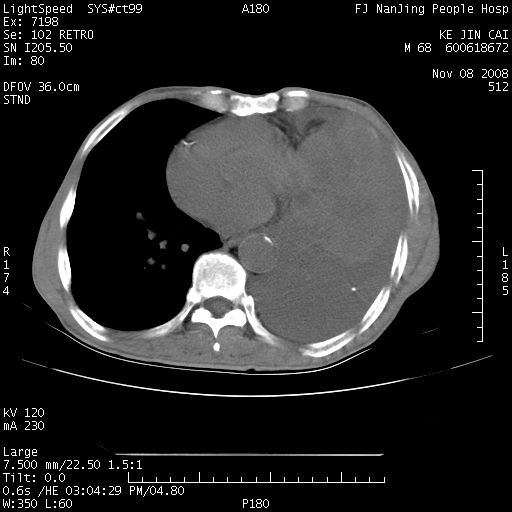

是个很有看头的病例,咋人气那么不旺?没多少人兴趣呢?这个病例几大怪:1   恶性肿瘤侵犯心肌左房怪,心肌一般不会被恶性肿瘤侵犯吧?2   左下肺均匀实变怪,内无含气,有别一般不张实变,含气肺泡完全为液体取代,而非一般不张实变的肺萎陷,冷不丁还以为是肿大的脾脏3   肿瘤本身怪,像tb肺不张4   这么有看头的病例没人气怪。呵呵。

左肺恶性肿瘤侵犯肺动脉,左心房内瘤栓,胸膜转移。

左肺恶性肿瘤侵犯肺动脉,左心房内瘤栓,胸膜转移,少见,学习了。